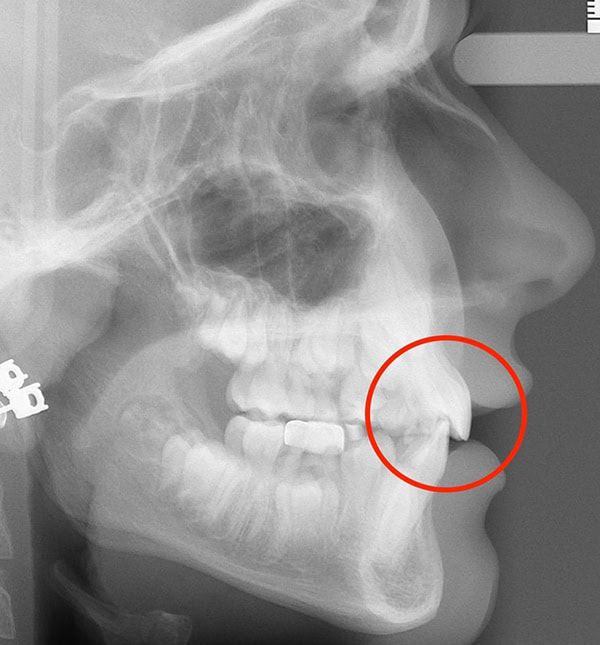

Actual Patient: Alexander

Alexander Before 4 Alexander After 4

Severe “Underbite”, Narrow Jaws, Adult Teeth Not Growing In

Alexander Before 1 Alexander After 1

Front View

Top View

Right & Left Sides